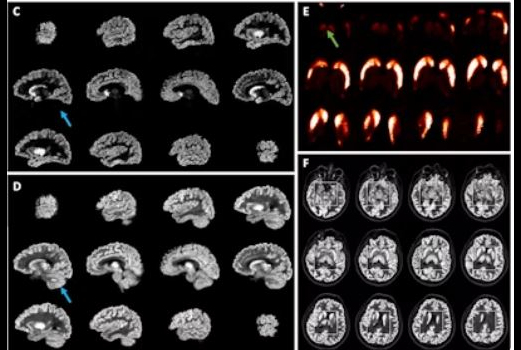

A major highlight at the annual meeting of the Society of Nuclear Medicine and Molecular Imaging (SNMMI) is always the Image of the Year award. You can see this year's winner in our special report from Toronto.

In another SNMMI article, Swiss researchers pointed out that an ultralow dose imaging method used with long axial field-of-view PET scanners produces images with a radiopharmaceutical dose 50 times lower than the standard effective dose. Also, make sure you check out AuntMinnie.com's news service from the conference.